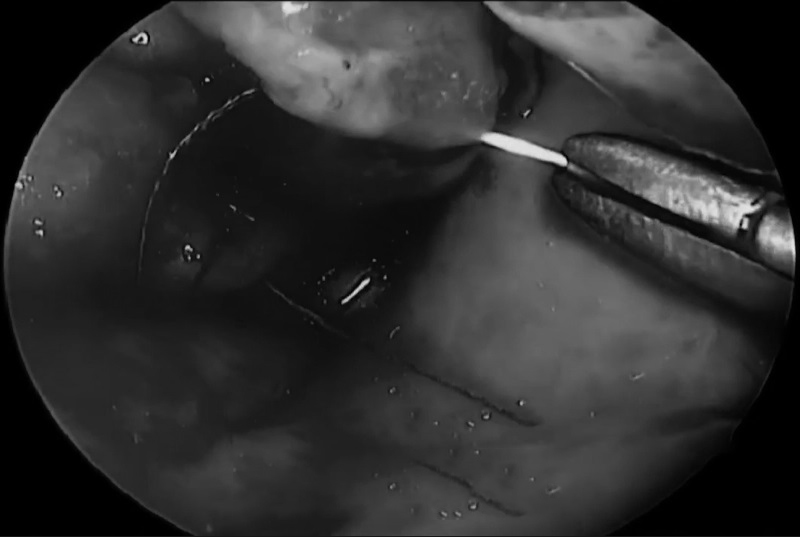

手术方案:通过对侧单鼻孔入路,左侧鼻中隔皮瓣切开并进行蝶窦切开术。

▼术后(C、D)图像显示病灶次全切除,并显示鼻中隔瓣修复良好。显示岩尖然后面的小部分残留病灶(C、D、箭头)。值得注意的是,除了鼻中隔后三分之二和蝶窦外,全部其他鼻内正常组织结构均被保留完整无损。